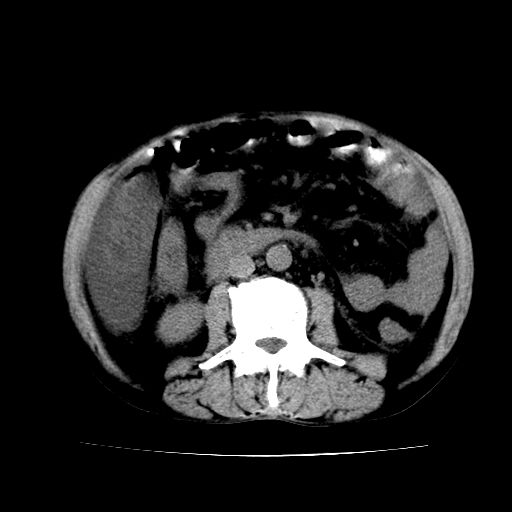

男,55岁,发现“肝硬化”5年,现腰疼、腹胀10余日,巩膜黄染、腹稍胀,肝肋下3指,质硬无压疼,移动性+,血生化:总胆、直胆、间胆均升高。

g1:肝硬化、脾大、腹水。

2:脂肪肝。

3:弥漫性肝癌待排。

肝硬化,脾大,腹水

脂肪肝

肝内多发低密度灶(建议增强扫描除外肝癌)

肝脾肿大,脂肪肝,腹水。建议增强除外肝癌。

1.脂肪肝

2.腹水

3.肝脾肿大

4.肝癌?

肝硬化,脂肪肝,腹水,肝癌